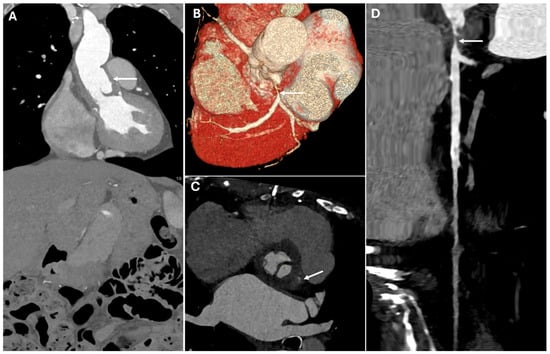

| Synthetic Grafts | Made of synthetic polyethylene. | Hyperattenuating relative to native aorta on noncontrast CT. Less apparent on postcontrast imaging due to adjacent blood pool. Lack flexibility, leading to straighter morphology and sharper angulations. | Sharper angulations and redundant folds may mimic dissection. |

| Stent grafts | Consist of a metallic skeleton covered with polyester. May include circumferential metallic rings or fenestrations for arch vessels. | Metallic framework appears hyperattenuating on CT. | Mimic calcifications or foreign bodies. |

| Reinforcement Materials | Felt rings, pledgets, sutures, and surgical clips used to strengthen anastomoses. | Hyperattenuating with beam-hardening artifacts. | Mimic calcifications, foreign bodies or pseudoaneurysms. |

| Bioabsorbable Hemostatic Agents | Used for intraoperative bleeding control. | Heterogeneous masses No air–fluid levels or enhancing walls. Linear arrangement of gas bubbles helps distinguish from infection. | Mimic abscesses, hematomas, tumors or retained foreign bodies. |

| Carotid-Carotid Bypass Grafts | Left carotid-subclavian graft often accompanied by proximal left subclavian artery occlusion. | Occlusion appears as hyperattenuating disk- or dumbbell-shaped structures. Grafts visible on multiplanar reconstructions. | Mimic calcifications |